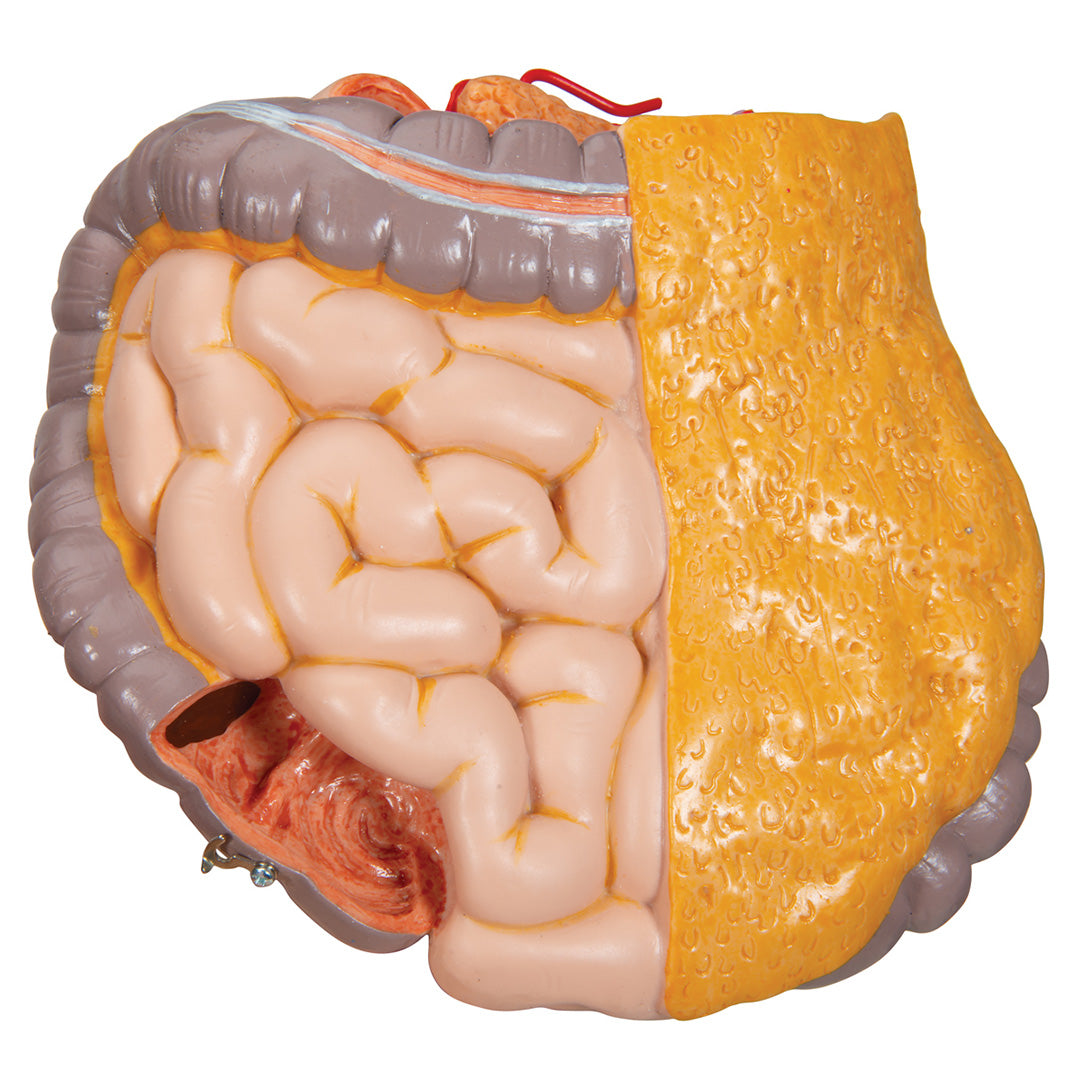

Sobre la anatomía interna humana.

• Paquete intestinal en 2 partes